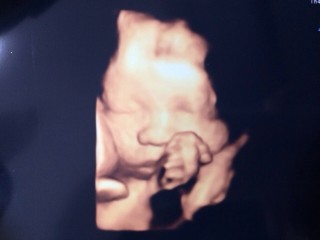

以前の4Dと比べて赤ちゃんらしくなりました! 赤ちゃんの胎動もあり、だんだん力強く蹴ってくるようになります